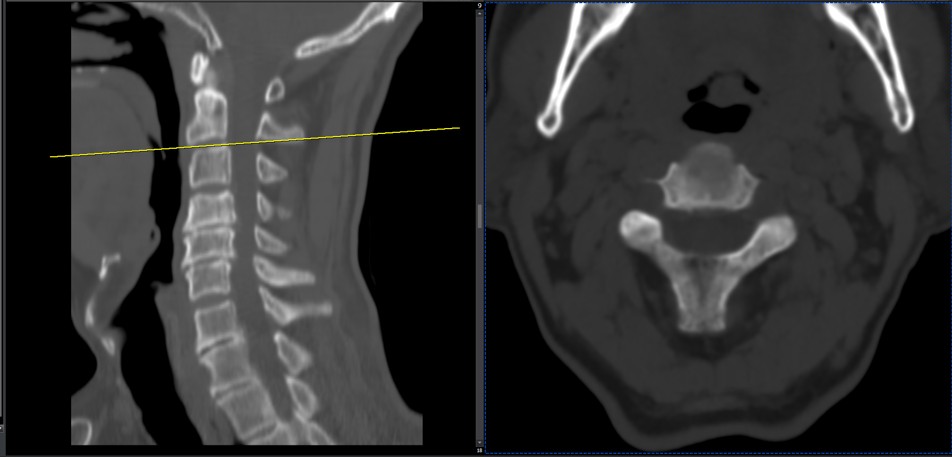

41 years old man presented to my clinic in October 2023 with acute and sever R neck pain with radicular pain to his R upper extremity along C6 dematom since 2 weeks ago. Examination didn’t show any upper motor signs. Was suggested urgent surgery

I ordered EMG/ NCV : showed mild R C6, C7 irritation without any active axonal loss

In his MRI was reported R. para R. IVF Massive extrusion. I decided to control his pain and manage this patient with reevaluation of patient every other session. For 5 sessions i just used acupuncture and laser and IFC and mild adjustments to his R. T3-T7 and mild arthosteem to above and below involved segment. Cervical adjustment considered contraindicated for this patient. From session 6th- 8th i started to use mild/gentle cervical decompression. He used soft cervical collar all the time. His pain decreased by 80 percent

I gave him cervical traction pump to be used 3-5 times per day at home for the next 3 months and i released the patient. He was evaluated every week once for one month and after that every 2 weeks. After 3 month I repeated MRI. Size of the herniated disc was reduced greater than 50 percent. Asked him to do another mri in 6 months

MRIs before and after proper management of this patient: